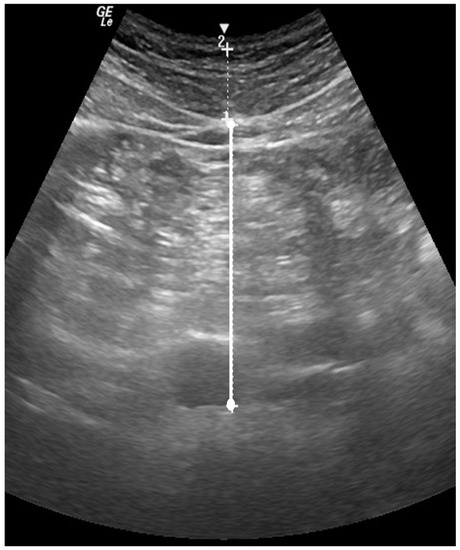

- Leite, C.C.; Wajchenberg, B.L.; Radominski, R.; Matsuda, D.; Cerri, G.G.; Halpern, A. Intra-abdominal thickness by ultrasonography to predict risk factors for cardiovascular disease and its correlation with anthropometric measurements. Metabolism 2002, 51, 1034–1040. [Google Scholar] [CrossRef]

- Stoner, L.; Chinn, V.; Cornwall, J.; Meikle, G.; Page, R.; Lambrick, D.; Faulkner, J. Reliability tests and guidelines for B-mode ultrasound assessment of central adiposity. Eur. J. Clin. Investig. 2015, 45, 1200–1208. [Google Scholar] [CrossRef] [PubMed]